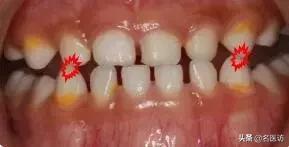

儿童乳牙 ”地包天”

怎么办?

什么是“地包天”?

专业地说,儿童乳牙期“地包天”,就是乳下前牙咬合于乳上前牙唇侧,也叫乳前牙反颌。

简单说,就是下面牙齿把上面牙齿款到了,限制了上面牙齿和骨头的发育。

“地包天”的后果

儿童“地包天”很有阔能引起娃娃身心都受挫哦!牙齿不整齐、下巴总是往前伸,不仅看起来不好看,还要影响咀嚼功能、发音、颞下颌关节发育,最恼火滴是对好多娃娃心理健康影响大,搞得娃娃都没得自信了!

当娃娃越长越大,症状还可能加重,下巴前突,面型畸变,更严重的还可能会变成朱元璋一样的“鞋拔子脸”、“半月脸”!